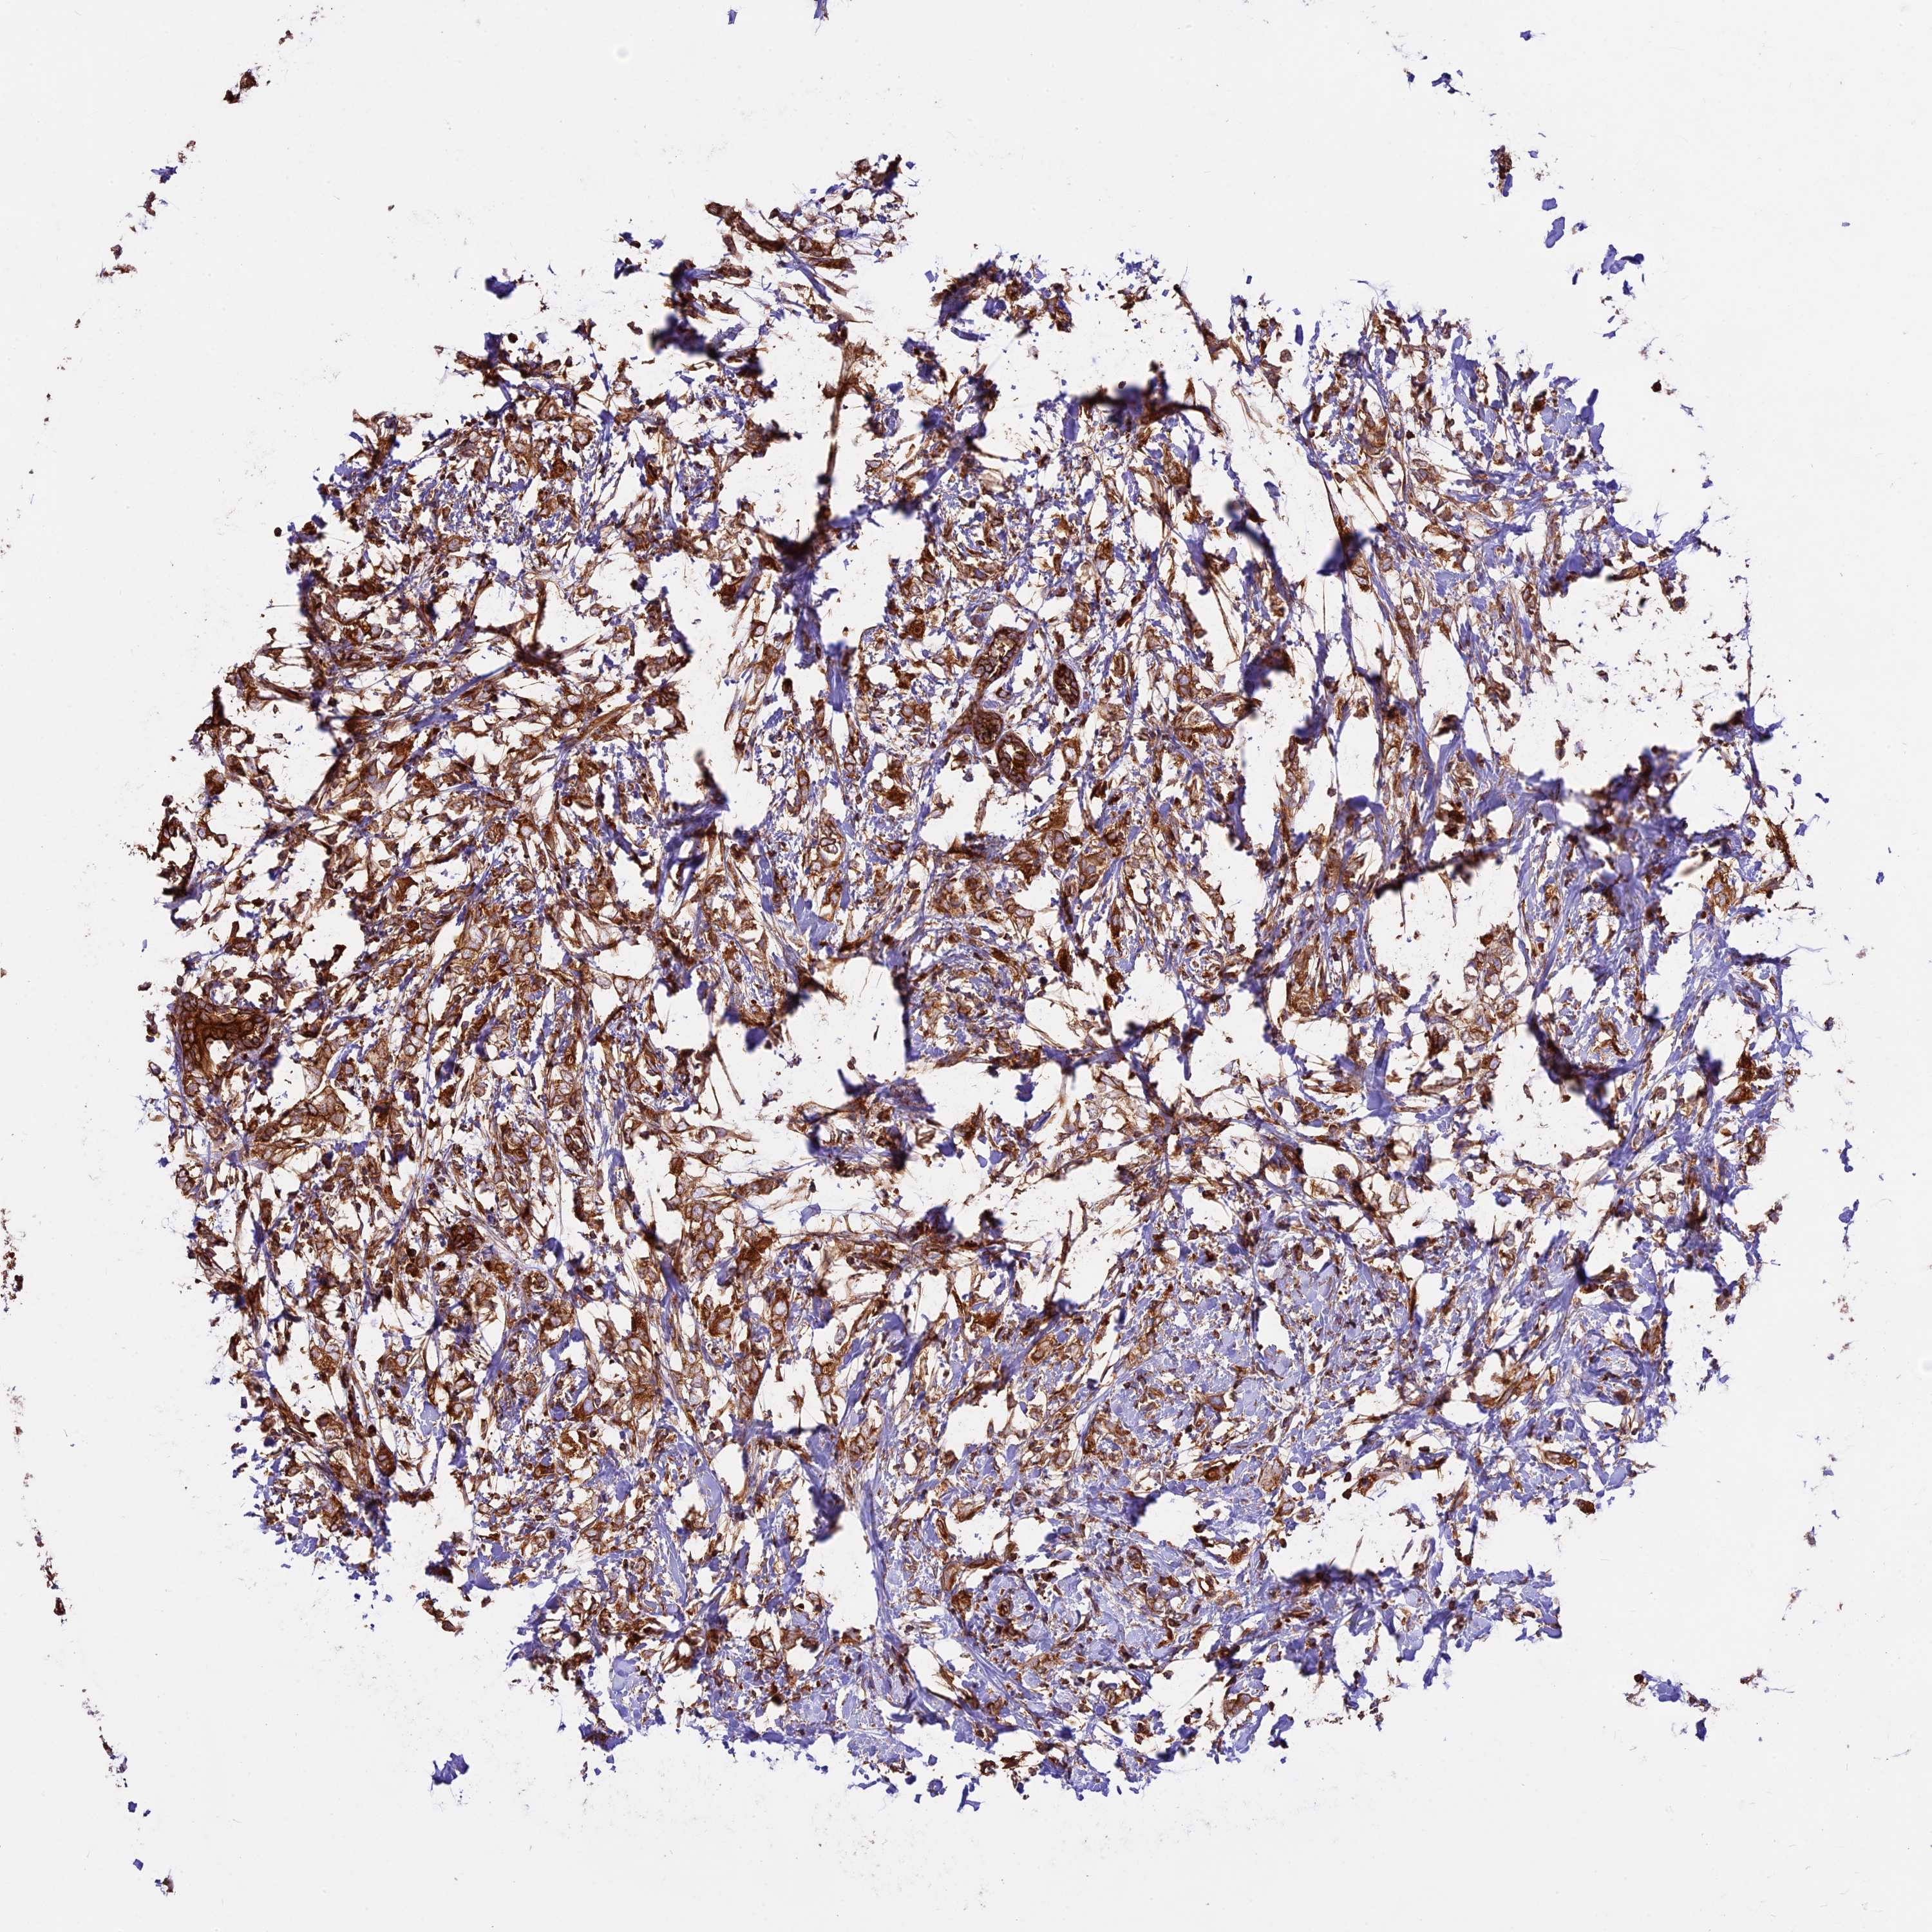

CANCER BREAST CANCER Show tissue menu

BRCA TCGA BRCA VALIDATION PROTEIN EXPRESSION